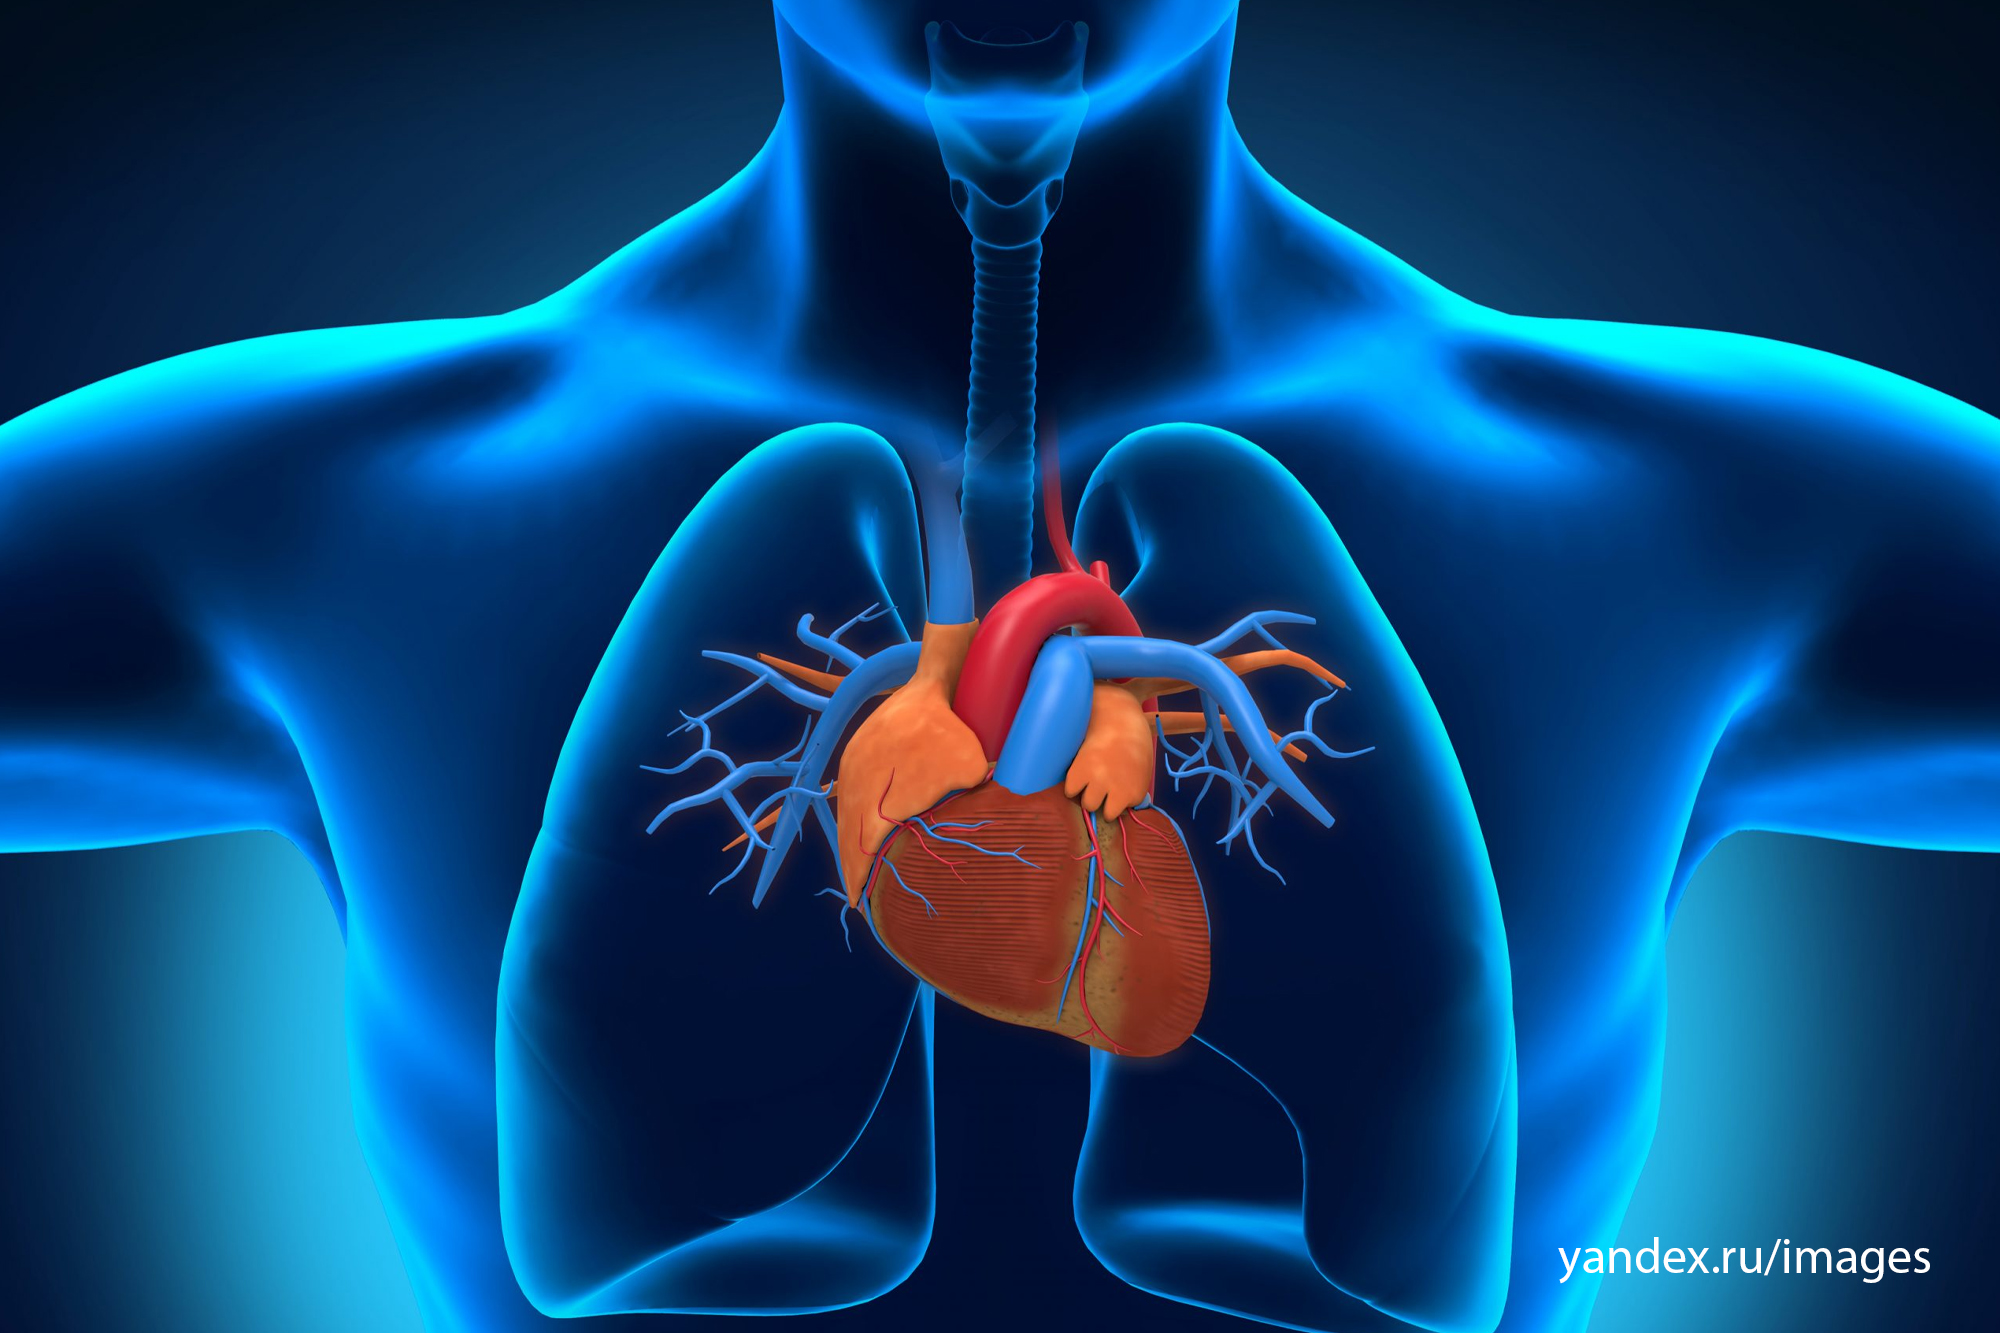

Где находится сердце у человека.

Сердце у человека располагается.

Сердце у человека располагается в грудной полости.

Сердце в грудной клетке расположено.